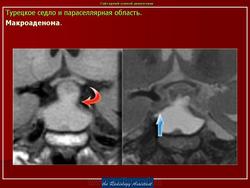

ГМ. Аденома гипофиза 1. +

Аденома гипофиза.